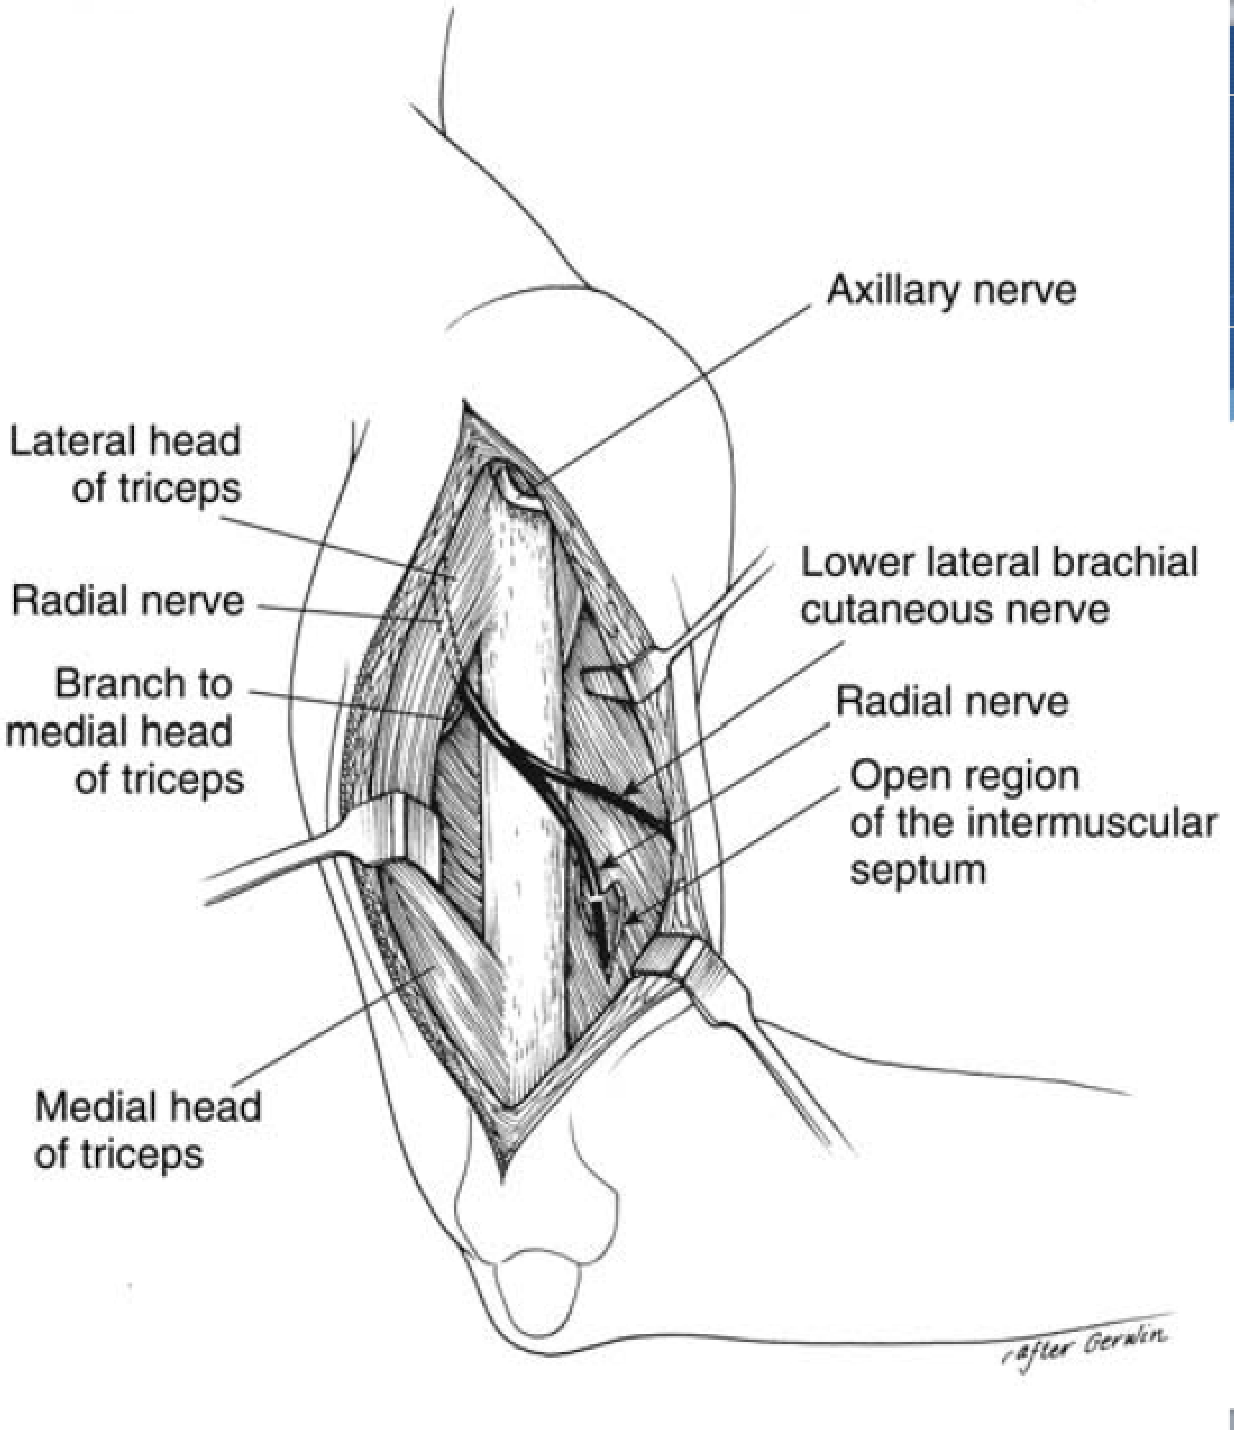

Paratricipital Approach

Interval: Lateral head of triceps (radial n.) and lateral intramuscular septum

Approach: Either identify LABCN (and trace to radial nerve proper) or radial nerve as it plunges into the intramuscular septum (~10cm proximal to the lateral epicondyle. Once radial nerve proper identified protect, peel triceps off of posterior humerus.

Dangers: Radial N. LABCN

* can do medial or lateral. Medially, radial nerve enters spiral groove ~14cm proximal to medial epicondyle. Ulnar nerve to be identified deep to brachioradialis.

Triceps Splitting Approach

Interval: No internervous plane, split triceps (radial n.)

Approach: Start 8cm distal to tip of acromion (distal to axillary n.). Split between long and lateral heads superficially, and split medial head deep. Care taken to mark out spiral groove and dissect radial nerve.

Dangers: Axillary N. proximally, radial n. in spiral groove.

*thought that this approach can de-innervate medial head of triceps